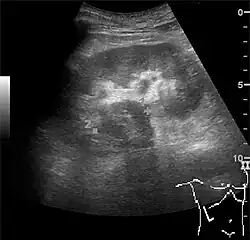

A solid renal mass appears in the US exam with internal echoes, without the well-defined, smooth walls seen in cysts, often with Doppler signal, and is frequently malignant or has a high malignant potential. The most common malignant renal parenchymal tumor is renal cell carcinoma (RCC), which accounts for 86% of the malignancies in the kidney. RCCs are typically isoechoic and peripherally located in the parenchyma, but can be both hypo- and hyper-echoic and are found centrally in medulla or sinus. The lesions can be multifocal and have cystic elements due to necrosis, calcifications and be multifocal (Figure 8 and Figure 9). RCC is associated with von Hippel–Lindau disease, and with tuberous sclerosis, and US has been recommended as a tool for assessment and follow-up of renal masses in these patients.[1]

However, US is not the primary modality for the evaluation of solid tumors in the kidney, and CT is the first choice modality. Nevertheless, hemorrhagic cysts can resemble RCC on CT, but they are easily distinguished with Doppler ultrasonography. In RCCs, Doppler US often shows vessels with high velocities caused by neovascularization and arteriovenous shunting. Some RCCs are hypovascular and not distinguishable with Doppler US. Therefore, renal tumors without a Doppler signal, which are not obvious simple cysts on US and CT, should be further investigated with CEUS, as CEUS is more sensitive than both Doppler US and CT for the detection of hypovascular tumors.[1]